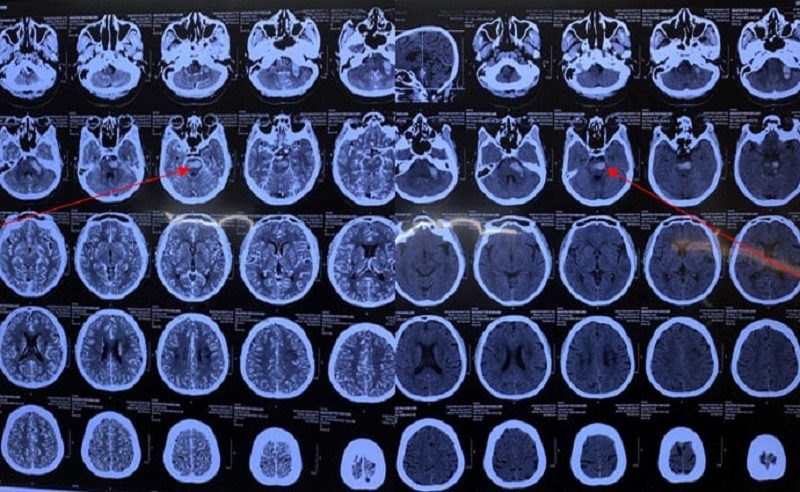

| Hình ảnh chảy máu thân não trên cắt lớp vi tính sọ não - Ảnh: BVCC |

Các bác sĩ cho biết, bà L. mắc Covid-19 kèm đột quỵ chảy máu thân não (xuất huyết não). Đột quỵ là bệnh phổ biến, có tỷ lệ tử vong cao, để lại nhiều di chứng nặng nề. Xuất huyết não tự phát mặc dù chỉ chiếm 10-20% trong tất cả các trường hợp đột quỵ nhưng tỷ lệ tử vong lên tới 37,6% - 52% vào tháng đầu và phần lớn tử vong trong 2 ngày đầu; gây tàn phế nặng nề.

Đột quỵ chảy máu thân não ảnh hưởng rất nhiều đến chức năng hô hấp của bệnh nhân do thân não hoạt động như trung tâm điều khiển chức năng của tim và phổi, giúp điều chỉnh nhiều chức năng quan trọng bao gồm thở, hắt hơi và nuốt.